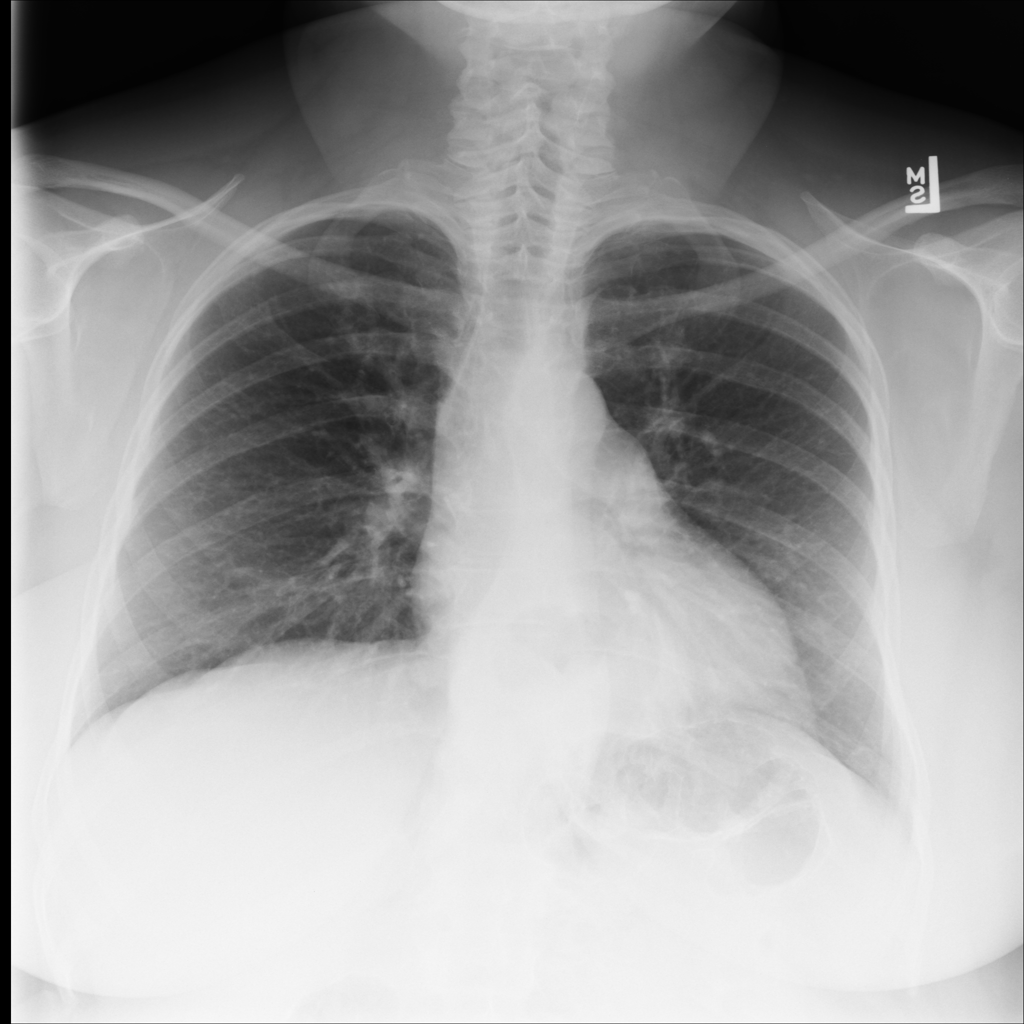

PAT-AE0E · IMG-000Hernia

PAT-AE0E · IMG-000

PA